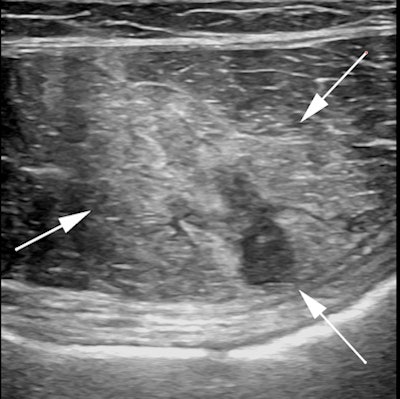

Professional tennis player with acute onset right groin pain during a match. Axial and coronal fat-saturated T2-weighted MR images demonstrate an acute injury of the right obturator externus muscle with a small focal hematoma. All images courtesy of Dr. Ara Kassarjian.